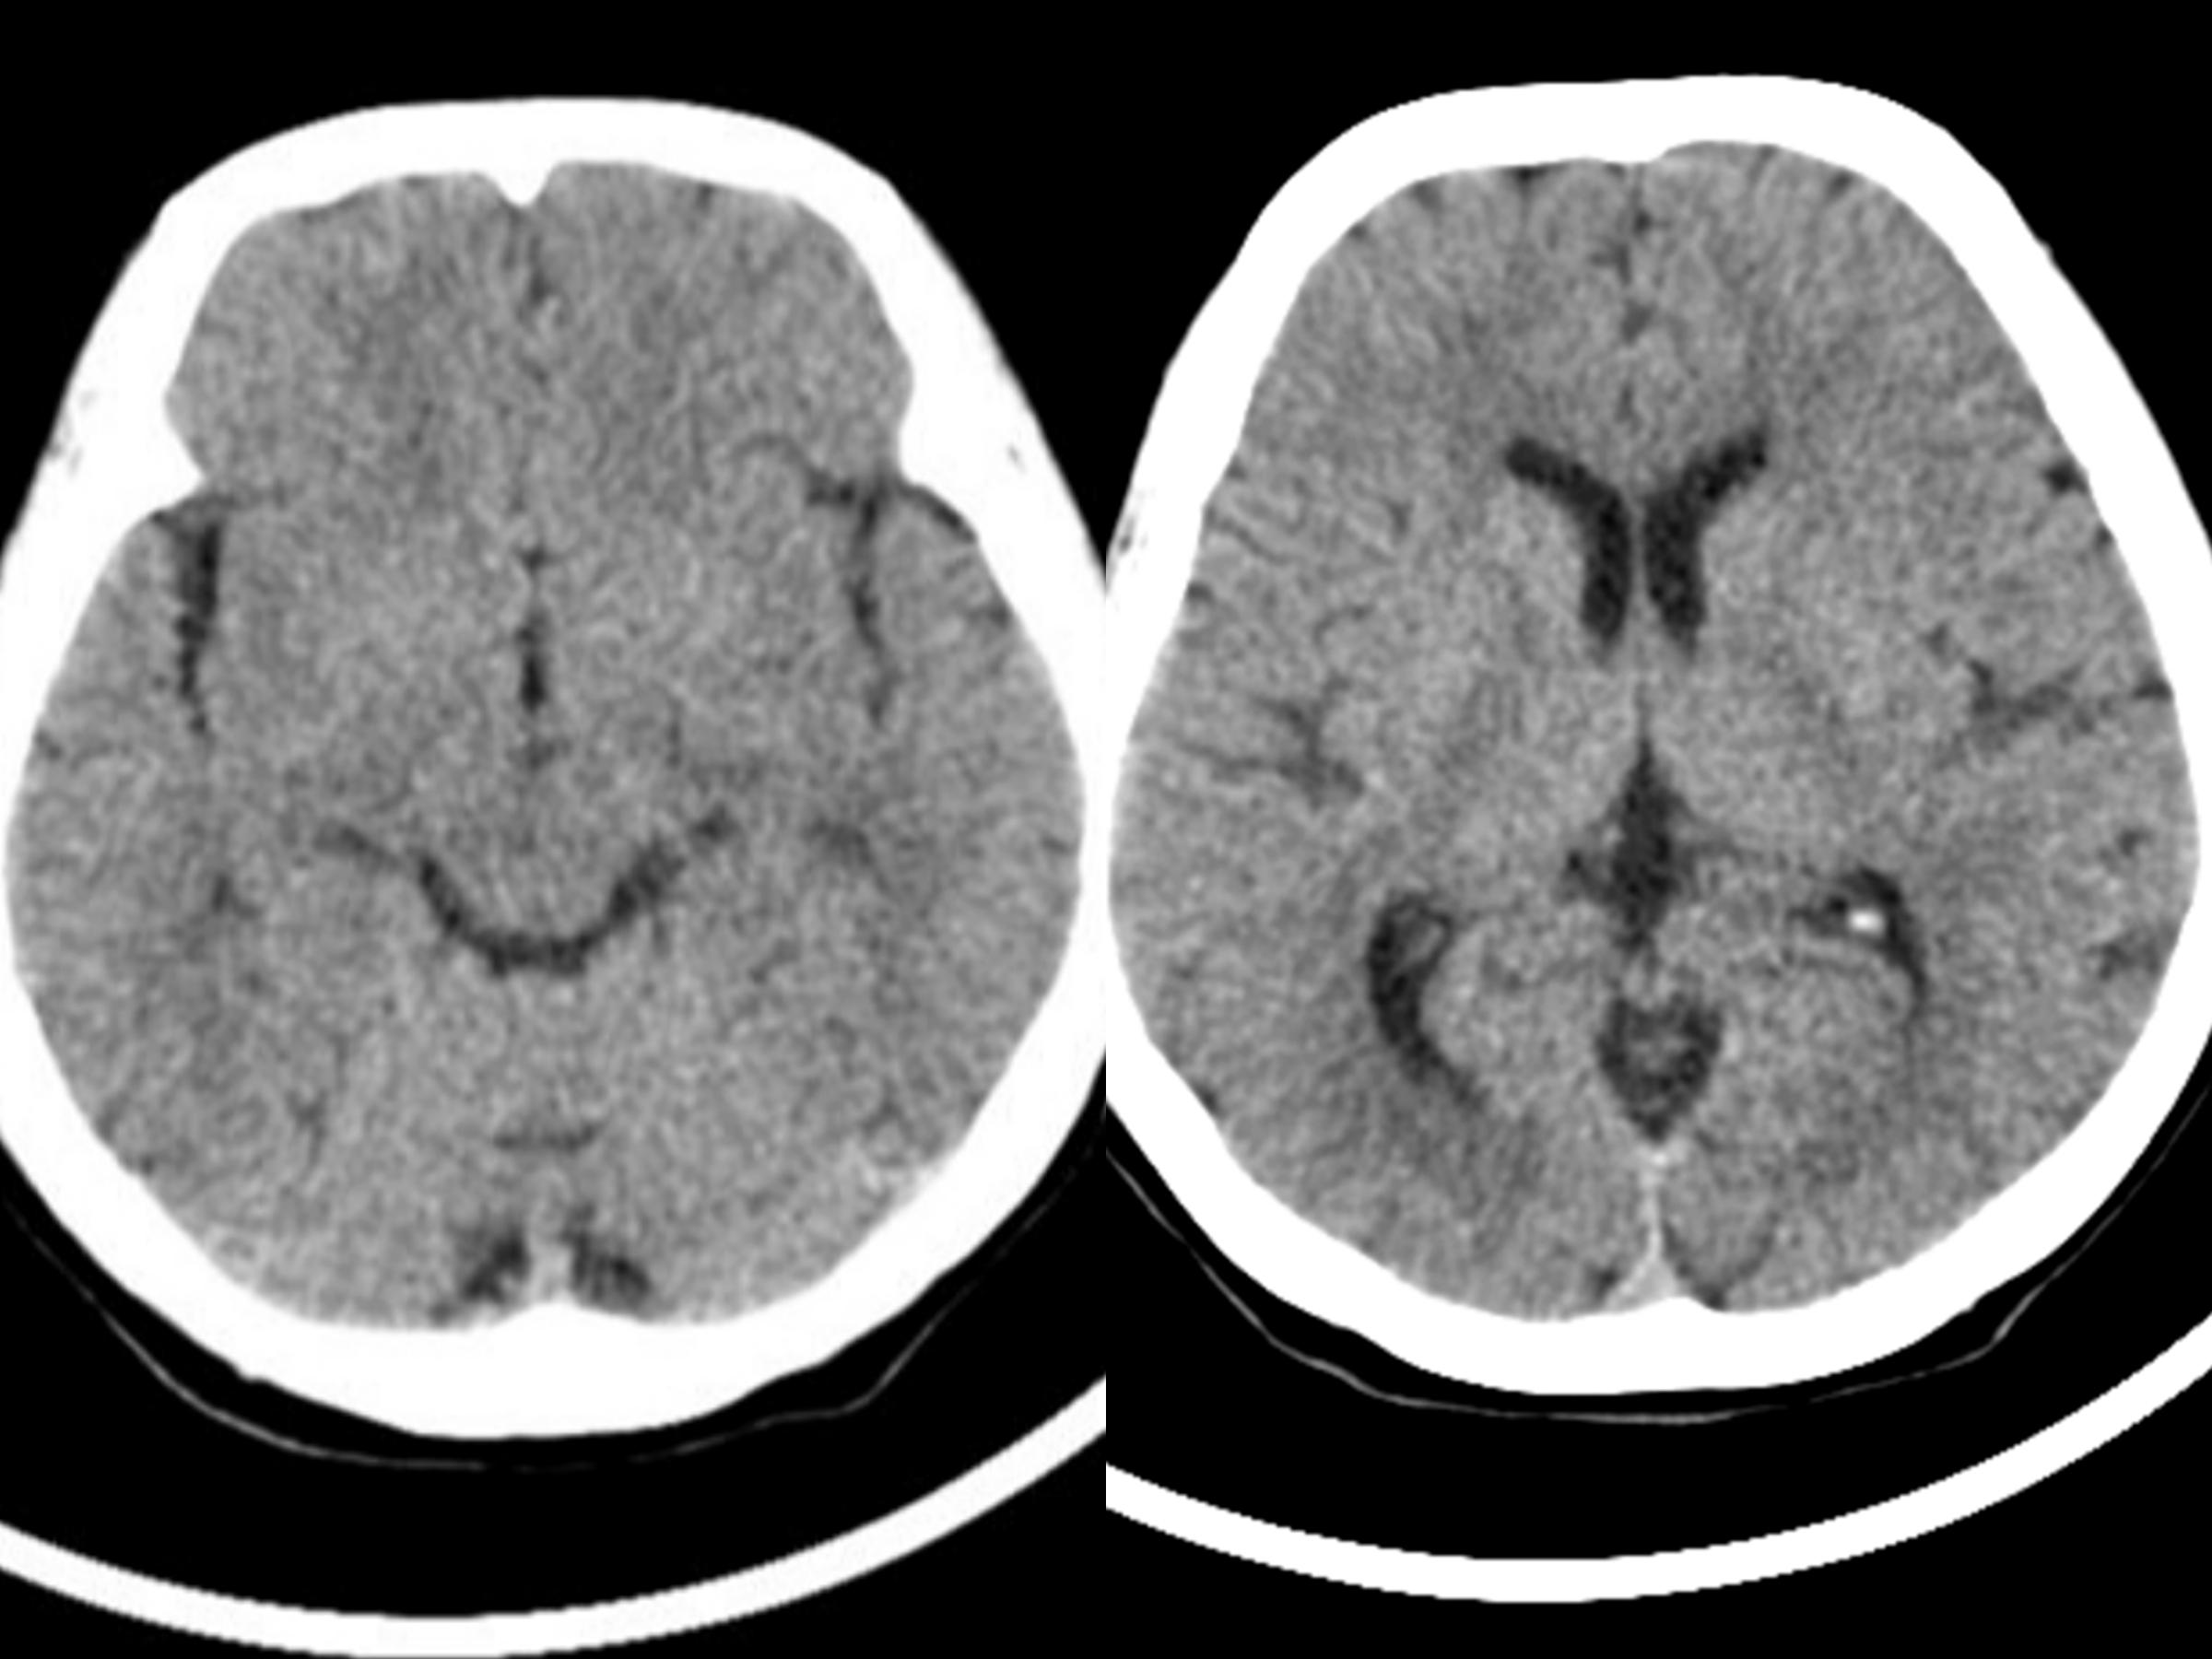

先来看看正常的大脑图像:

CT检查正常的大脑

MRI检查正常的大脑